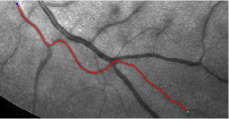

In this paper, we propose a coherence-penalized minimal path model, where the associated minimal paths favour to pass by a vessel that is located in the flatten region of an external feature map. We observe that along a piece of retinal vessel, the values of gray levels vary slowly. More specifically, retinal arteries have lower contrast of gray levels than veins due to the blood materials and imaging modality. In other words, in some extent the arteries and veins are distinguishable in terms of vesselness values. Such an observation can be used to solve the short branches problem that the minimal paths associated to a metric may pass through segments belonging to different vessels as shown in Figs. 1b and 1c. Fig. 1d shows the result from the proposed method, which can avoid such problem. Fig. 1a gives the artery-vein (AV) groundtruth. In this paper, we denote by blue and green dots the source and end points respectively.

Validation. We validate our minimal path model on respective 54 and 30 patches obtained from the DRIVE [14, 15] and the IOSTAR [16] datasets with AV groundtruth. Each artery involved in these parches locates near a vein or crossing it at least once. Our goal is to extract the artery between two given points. In order to get the quantitative evaluation, we first convert each continuous spatial path to an 4-connected digital path which is considered as a pixel collection. We denote by the collection of digital path pixels inside the artery groundtruth map . Thus, a measure can be simply defined as , where and mean the respective number of elements involved in and . We compare our model to four existing minimal path models: the isotropic Riemannian (IR) model [1], the anisotropic radius-lifted Riemannian (ArR) model [4], the isotropic orientation-lifted Riemannian (IoR) model [5] and the curvature-penalized (CuP) model [7]. The construction of these metrics are based on the OOF outputs [12]. Note that a centerline-based potential is chosen so that we remove the radius dimension of [5] to reduce computation complexity. The results in terms of the score are presented in Table 1, including the average (Avg.), maximum (Max.), minimum (Min.) and standard deviation (Std.) values. In both DRIVE and IOSTAR datasets, our method can achieve the best performances thanks to the coherence penalization. Note that in Table 1, we evaluate our method by using the refined paths instead of using the original coherence-penalized minimal paths. For comparisons in visualization, we show the minimal paths from the ArR metric , the CuP metric and the proposed coherence-penalized metric on three retinal patches as shown in Fig. 3. The targeted artery vessels which cross veins at least once are labeled by red color in column 1. The paths shown in column 4 from the proposed metric are results after refinement. One can claim that our method indeed can catch expected arteries while other metrics fall into the traps of short branches combination.